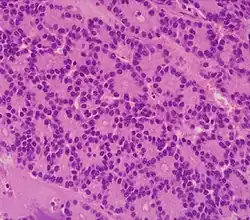

The most common form of pancreatic cancer (adenocarcinoma) is typically characterized by moderately to poorly differentiated glandular structures on microscopic examination. There is typically considerable desmoplasia or formation of a dense fibrous stroma or structural tissue consisting of a range of cell types (including myofibroblasts, macrophages, lymphocytes and mast cells) and deposited material (such as type I collagen and hyaluronic acid). This creates a tumor microenvironment that is short of blood vessels (hypovascular) and so of oxygen (tumor hypoxia).[2] It is thought that this prevents many chemotherapy drugs from reaching the tumor, as one factor making the cancer especially hard to treat.[2][3]

| Cancer type | Relative incidence[11] | Microscopy findings[11] | Micrograph | Immunohistochemistry markers[11] | Genetic alterations[11] |

| Pancreatic ductal adenocarcinoma (PDAC) | 90% | Glands and desmoplasia | ![]() |

|

| Pancreatic neuroendocrine tumor | 5% | Multiple nests of tumor cells | ![]() |